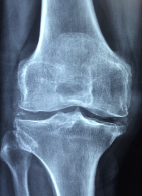

뼈 관절에 좋은 음식 및 뼈 관절에 관한 정보에 대해 알아보도록 하겠습니다. 뼈 관절은 뼈를 서로 연결하여 움직임을 가능하게 하는 부위를 말합니다. 뼈 관절은 인체의 운동 기능을 수행하는 중요한 역할을 하며, 뼈와 뼈, 뼈와 근육, 뼈와 연골 등 다양한 부위에서 발생합니다. 뼈 관절은 크게 공동강, 일반강, 역삼각형, 공동강, 원형관절 등의 형태로 나누어집니다.뼈 관절은 움직이는 부위이기 때문에 과도한 운동이나 부상, 노화 등으로 인해 손상될 수 있습니다. 뼈 관절에 생기는 문제로는 골관절염, 류마티스 관절염, 슬관절염 등이 있으며, 이러한 질환은 통증, 염증, 운동 제한 등의 증상을 유발할 수 있습니다.

뼈 관절 통증은 다양한 원인에 의해 발생할 수 있으며, 통증의 정도와 위치는 개인에 따라 다를 수 있습니다. 그러나 일반적으로 뼈 관절 통증은 다음과 같은 증상을 보일 수 있습니다.

뼈 관절 통증 원인

뼈 관절 통증의 원인은 다양합니다. 일부 경우에는 부상, 비만, 노화 및 과도한 운동 등에 의해 발생할 수 있습니다. 뼈 관절 통증의 원인 중 일부는 다음과 같습니다.

- 골관절염: 골관절염은 뼈 관절의 조직 손상과 염증에 의해 발생하는 통증입니다. 통증과 함께 관절이 부어오르고 강직해지는 증상을 보입니다.

- 슬관절염: 슬관절염은 무릎 관절의 손상 및 염증으로 인한 통증을 보입니다.